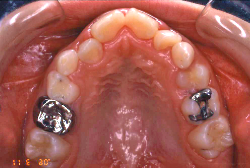

診断の結果、典型的なアングル2級1類の上顎前突です。上下歯列の正中の不一致も見られます。しかし、歯の大きさは平均値に近く、配列の凸凹がそれほど見られません。このまま放置すると、将来的には抜歯を伴う矯正治療を行う可能性が高くなりますが、このタイミングで適切な治療をすると、非抜歯治療が可能かもしれません。

矯正歯科医が着目するのは、奥歯の噛み合わせの位置関係です。前歯の位置にそれなりの差が生じていても、奥歯の位置が正しければそれほど重症という評価にはなりません。このケースの場合は、上下の第一大臼歯の位置関係は、直線的に一致しているタイプでした(矢印が一致)。混合歯列時期の奥歯の位置関係としては、ほぼ正常な状態といえますが、症状から言うと、上の奥歯をもっと後ろに下げてやることができれば、上顎歯列全体に余裕ができるので、凸凹も解消できるし、前歯の傾きを内向きに修正することもできると考えられました。しかしこのまま全体に永久歯が生えきってしまうと、上の前歯が出たままになってしまいますので、生え替わりが完了する前に大急ぎで奥歯を後ろに下げる必要があると判断しました。

こういう症状でもっとも効果があるのが、顎外固定装置と言って、お口の外部から奥歯に力をかける方法です。 写真の装置はネックバンドというタイプの装置です。この装置は取り外し式ですので、夜寝るときに毎日自分で取り付けて、寝ている間に少しずつ上の奥歯を後ろに下げていきます。この装置には、奥歯を後ろに下げる効果だけでなく、上顎の過剰な成長発育の抑制、下顎の成長促進作用があるとされており、上顎前突の症状にはいずれも有利な効果が期待できます。

ネックバンドを1年半使用して、上顎大臼歯が十分後ろに下がったところで、裏側にリンガルアーチという固定のワイヤーを取り付けて、新しく生じた隙間が狭くならないよう「保隙(ほげき)」という処置をして、永久歯が生えそろうまで待機中の様子です。配列全体に隙間が生じているのがお分かりいただけると思います。これだけの隙間が確保できていれば、抜歯をしなくても、あとで上の前歯を内側に理想的な角度で引っ込めることができます。このように完全に永久歯列になる前に、十分な隙間が確保できるかどうかが、非抜歯で矯正できるかどうかの分かれ目になります。